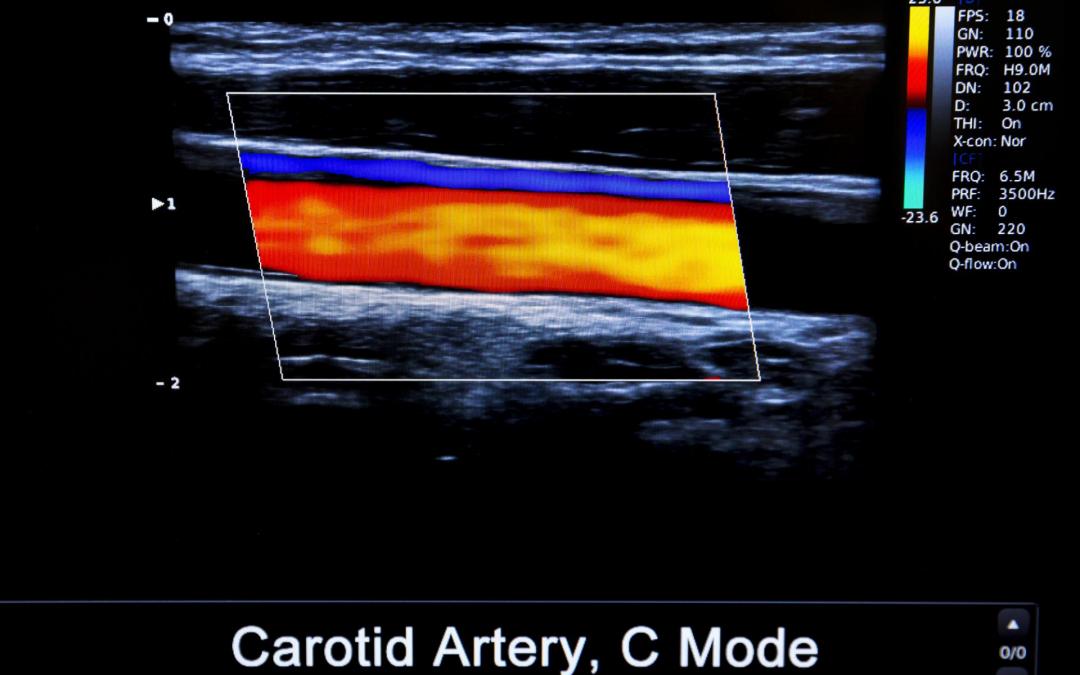

USG Doppler tętnic kończyn dolnych: kiedy podejrzewać miażdżycę/PAD i jak wygląda badanie? (Warszawa) USG Doppler (USG duplex) tętnic kończyn dolnych to nieinwazyjne badanie, które pokazuje przepływ krwi w tętnicach, wykrywa zwężenia i zamknięcia (najczęściej...